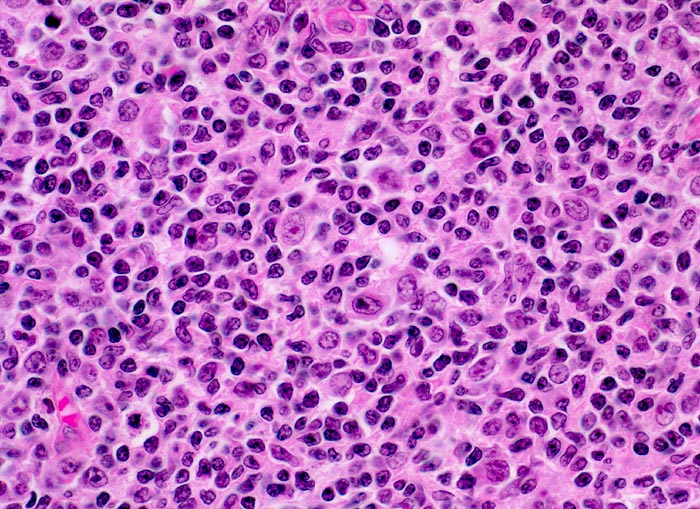

PathoPic – image database / PathoPic ID 3881 - Follikuläres B-Zell Non-Hodgkin-Lymphom: neoplastisches Keimzentrum

Follikuläres B-Zell Non-Hodgkin-Lymphom: neoplastisches Keimzentrum

Neoplastisches auffallend monotones Follikelzentrum bestehend aus kleinen lymphoiden Zellen mit eckigen Kernen, kaum erkennbaren Nukleolen und wenig Zytoplasma (Zentrozyten). Daneben finden sich grössere follikulär dendritische Zellen mit blassem Kernchromatin, zentralen Nukleolen und hellem Zytoplasma mit hier kaum sichtbaren fein ausgezogenen Ausläufern.

Die Keimzentren sind immunhistochemisch positiv für bcl-2.